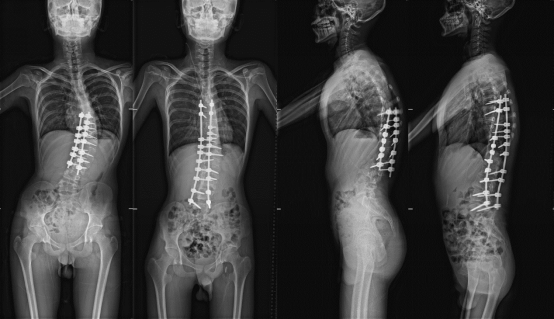

五年的持续跟踪治疗,更换了四副支具,随着孩子进入青春期,身高长到1.65米,畸形再次加重,支具治疗已经不能阻止畸形进展,出现了明显的躯干偏移。

今年3月,福建省立医院骨科与运动医学中心为患者做了第二次手术,基本矫正了畸形,融合节段延长,术后身高达到1.73米。